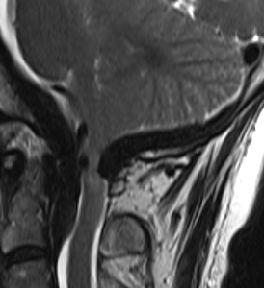

2015-4-1 MRI

2015-3-31

脑压100

2015-4-1